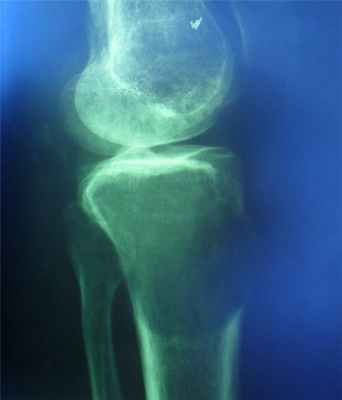

Опухолевая деструкция. Деструкция на почве злокачественной опухоли характеризуется наличием сплошных дефектов вследствие разрушения всей костной массы как губчатого, так и коркового слоя в связи с инфильтрирующим ее ростом.

При остеолитических формах деструкция обычно начинается с коркового слоя и распространяется к центру кости, имеет смазанные, неровные контуры, сопровождается обрывом и расщеплением краевой компактной кости. Процесс в основном локализуется в метафизе одной кости, не переходит в другую кость и не разрушает замыкающую пластинку суставной головки, хотя эпифиз или его часть может быть расплавлена совсем. Сохранившийся свободный конец диафиза имеет неровный, изъеденный край.

Деструкция при остеобластическом или смешанном типе остеогенных сарком характеризуется сочетанием участков разрушения кости, которые отличаются наличием хаотической костной структуры с избыточным атипичным костеобразованием; проявляющимся округлой или веретенообразной тенью вокруг мало разрушенной основы кости. Основным признаком, свидетельствующим о злокачественном характере указанных опухолей, остается отсутствие резкой границы между участками деструкции и неизмененной костью, а также разрушение коркового слоя.